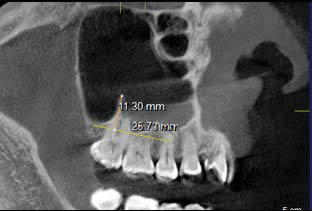

De acuerdo a su origen, existen dos tipos de septos: los primarios y los secundarios. Los primarios o llamados también septos congénitos, se forman durante el desarrollo de la zona central de la cara, originándose de la fusión de residuos durante la formación del seno maxilar (12), (figura 2 y 3); sin embargo Underwood relaciona su origen con las piezas dentarias justificando que se forman por separaciones intermedias del piso antral debido al desarrollo radicular (14). Autores como Lee et al., mencionan que los septos se originan por proyecciones digitales debido a la invaginación del infundíbulo etmoidal durante el desarrollo embrionario donde las paredes adyacentes no se reabsorben (2).

Los septos secundarios, tienen un origen adquirido asociado a atrofia del hueso maxilar como consecuencia de pérdida de dientes, siendo más frecuentes en el piso del seno. La longitud de éstos septos suele ser inferior que los primarios (2,7,12,15,16,17,18). (figura 4 y 5). Gonzales et al., consideraron septos primarios a aquellos donde hay piezas dentarias presentes y los septos secundarios en zonas edéntulas (6).

Se encontraron 298 (65,1%) septos unilaterales y 160 (34,9%) bilaterales (tabla 3); considerando lado, la frecuencia de septos predominó en el lado derecho con 234 y el lado izquierdo presentó un total de 224 septos (tabla 4). La longitud promedio de septos congénitos fue de 5,8mm y para otros septos fue de 5.6mm. El valor p fue igual a 0,523 lo que indica que no hay diferencias estadísticamente significativas entre ambos grupos (tabla 5).